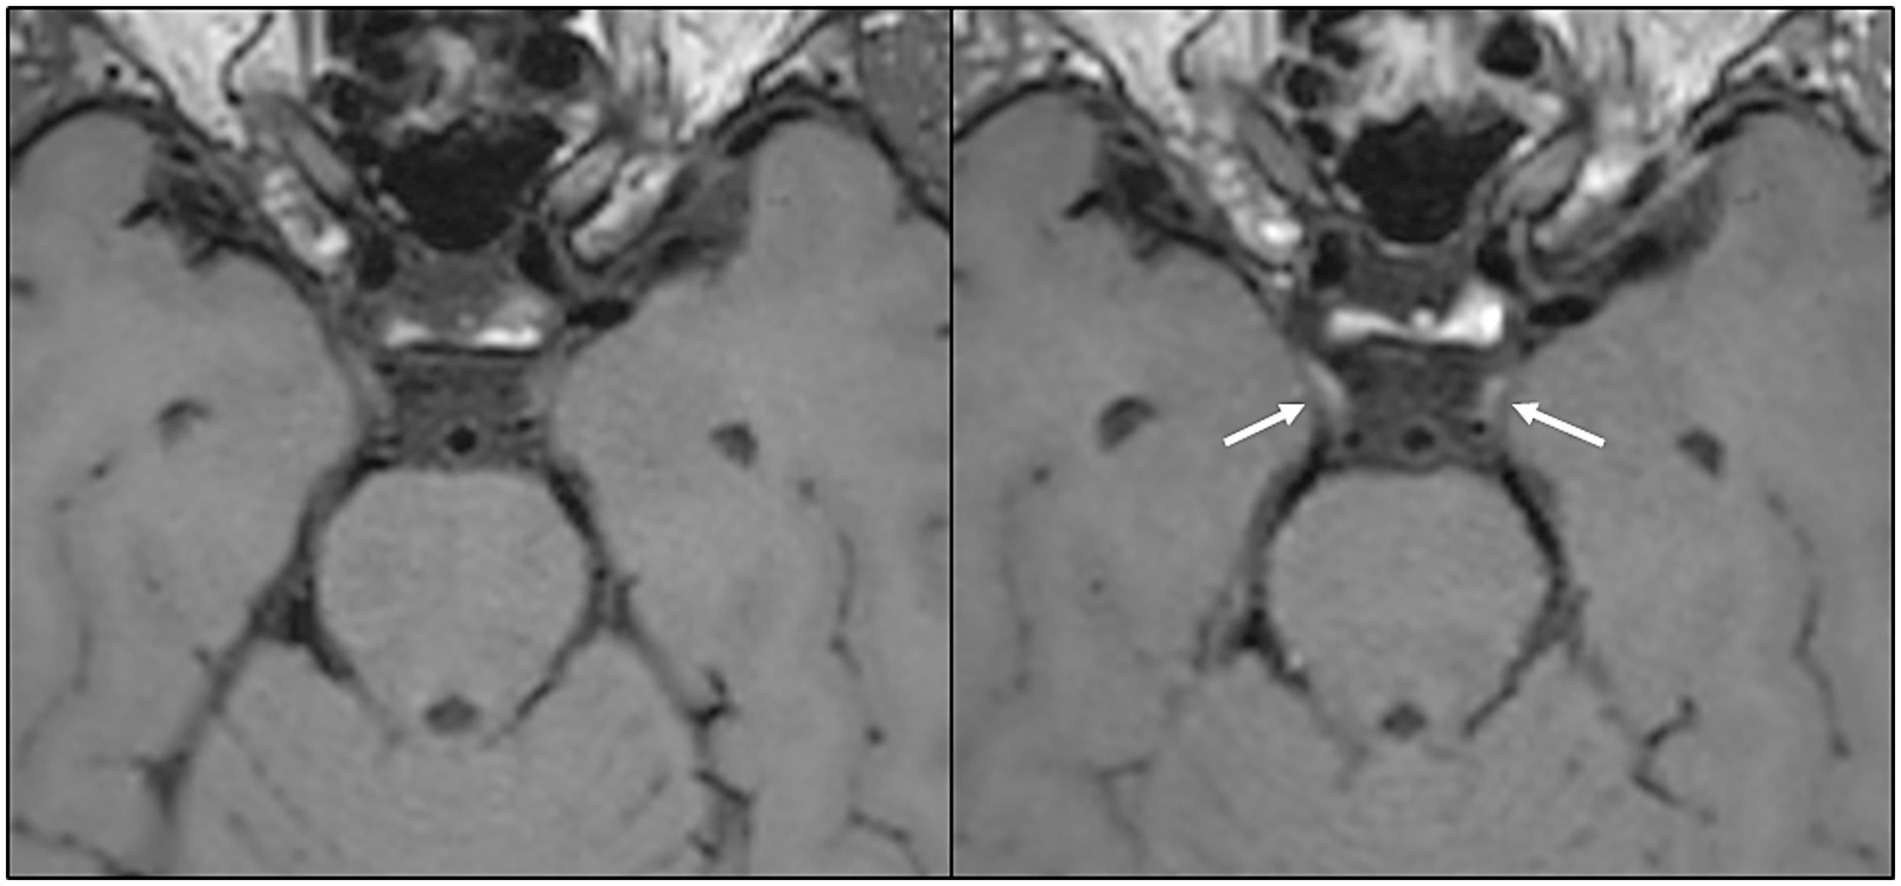

Background: Prolonged neurological symptoms following COVID-19 are common, yet few longitudinal studies describe brain MRI findings in this patient group. The use of contrast enhanced sequences is particularly lacking. We address this knowledge gap by reporting the frequency and longitudinal changes in brain MRI findings among patients with post COVID-19 condition exhibiting neurological symptoms. Methods: This prospective multicenter study included 140 adult patients referred for persistent neurological symptoms following COVID-19. Brain MRI was performed at both six and 12 months after infection onset, reporting white matter hyperintensities, cerebral microbleeds, and additional pathological findings including contrast enhancement. White matter hyperintensities were compared with a healthy control group. Results: The prevalence of white matter hyperintensities was comparable to healthy controls, and microbleeds were found at rates comparable to population studies, with longitudinal changes being infrequent. Lesions consistent with inflammation or demyelination were present in 4% (5/120) of patients at six months. Cranial nerve enhancement was found in 7% (7/94) of patients, persisting up to 12 months, predominantly affecting the oculomotor nerve. However, enhancement occurred without clinically detected ocular muscle paresis. Conclusion: Our findings indicate that brain MRI primarily serves to exclude differential diagnoses in post COVID-19 condition, with limited clinical benefit of repeated imaging in the absence of new symptoms. However, signs of long-term inflammatory processes can be observed, and detection is improved by contrast enhanced sequences.